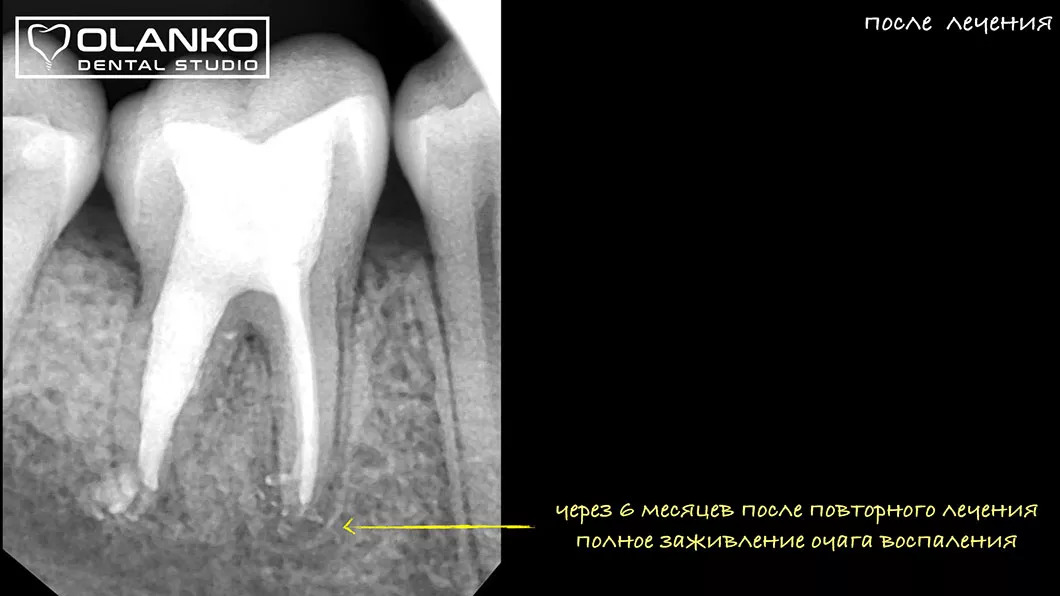

Мы имеем огромный клинический опыт лечения зубов со сложной анатомией (искривлёнными, склерозированными каналами), а также повторного перелечивания каналов с кистами, гранулемами, сломанными инструментами, с последующими отличными результатами заживления очагов хронического воспаления.

Для лечения простых клинических случаев, как правило, требуется всего один визит длительностью 1,5-2,5 часа.

Сложные случаи перелечивания корневых каналов, искревлённых каналов со сложной анатомией, требуют 2-3 визитов.